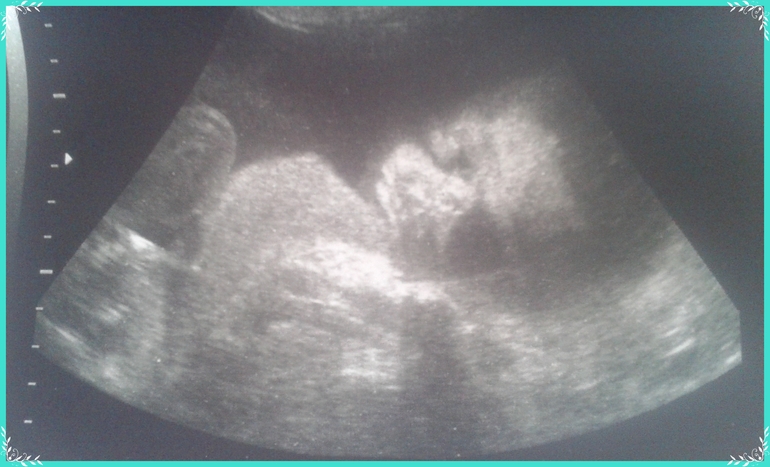

Малыш на узи как всегда вел себя спокойно, дал тете-врачу посмотреть все, что надо. Правда, фото с 3д получились смазанными, малыш на них прятался, но кое-что удалось заснять обычным узи)))

И так наши результаты:

1. Срок по узи (как в прочем и на всех узи) опережает - поставили 25 недель

2. Вес уже 870 г - вот это сыночек Богатырь

3. Плацента по передней стенке, 0 степень зрелости, 24 мм толщиной

4. ЧСС - 146 уд в мин

5. По Доплеру все протоки в норме! Обвития нет))))

Малышок лежал головой вниз как и положено - послушный мальчик)) услышал просьбы мамы

И фоточка моего карапуза (пока не понимаю на кого похож, вроде на мужа, а вроде и на меня):